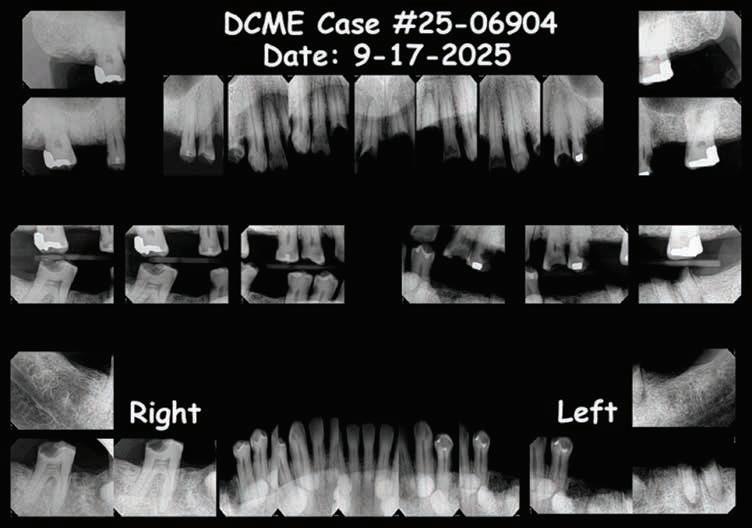

Unidentified Individual: Dallas County Medical Examiner (DCME) Case #25-06904, NamUs #UP144096

Dental Evidence Recovered: Maxilla and Mandible

Maxilla Occlusal View

Mandible Occlusal View

Right Left

Right Lateral View

Left Lateral View

Right Left Left Right

Dental Postmortem Radiographs

DCME Case #25-06904:

If you believe you have any dental records, dental radiographs, intraoral/extraoral dental photographs, dental scans or other dental information regarding the unidentified Black male decedent described above as DCME Case #25-06904/ NamUs #UP144096, please contact the Dallas County Medical Examiner’s Office, 214-920-5900, ask for Steven Kurtz, chief medicolegal death investigator or Keara St Louis, deputy chief medicolegal death investigator.